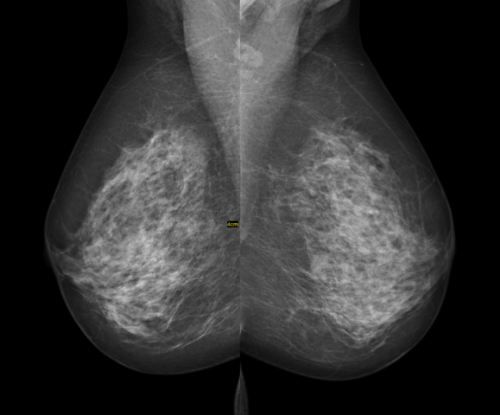

Three-dimensional (3D) breast mammography (Figure 1) is superior to conventional digital mammography for the detection of breast malignancies according to the results of a systematic review published recently in The Breast.

(Sources: Wikipedia/Creative Commons/Wikimedia/By ©Nevit Dilmen).